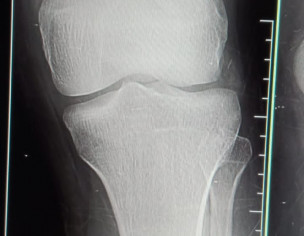

My fiance had an accident a month ago and then he had an x-ray but the bone was not broken at that time but still the pain was not getting less. So the injured leg is getting weak and he is not being weighed. he does not walk faslty and can't go up the give a good advice. Need your kind response.

Xray is ok get an MRI knee

There is no bone fractured but may be ligaments injury that won’t be visible in xray, so get checked up by Orthopedic surgeon and or get MRI done n share